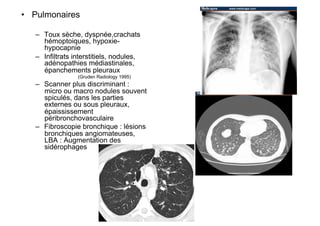

•  Pulmonaires

–  Toux sèche, dyspnée,crachats

hémoptoiques, hypoxie-

hypocapnie

–  Infiltrats interstitiels, nodules,

adénopathies médiastinales,

épanchements pleuraux

(Gruden Radiology 1995)

–  Scanner plus discriminant :

micro ou macro nodules souvent

spiculés, dans les parties

externes ou sous pleuraux,

épaississement

péribronchovasculaire

–  Fibroscopie bronchique : lésions

bronchiques angiomateuses,

LBA : Augmentation des

sidérophages